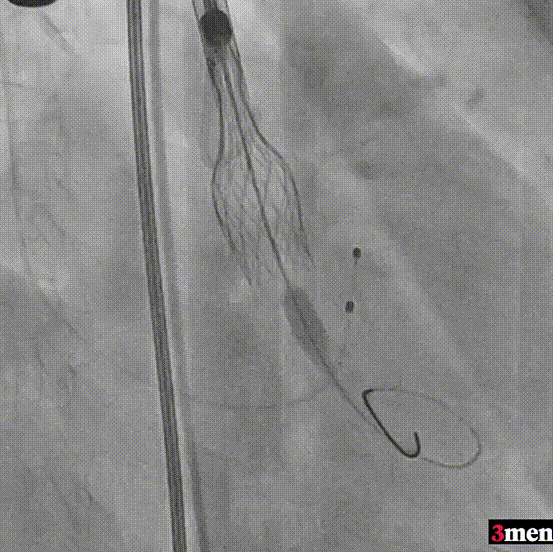

手术过程回顾:

患者全麻后,右侧股动脉建立主入路,主动脉根部造影显示主动脉瓣明显钙化。心室内轻微反流,主动脉及心脏情况整体较为稳定。直头导丝跨瓣后,在超硬导丝支撑下,瓣膜输送系统顺利跨瓣。在180次/分快速心室起搏下,确定降压至50mmHg后选择18mm球囊进行预扩张。在球囊扩张后,该患者血压未见升高,随即进行胸外按压,同时根据术前评估及球囊预扩情况,选取直径23mm瓣膜果断快速进行瓣膜定位并释放。瓣膜释放后患者心律和血压趋于平稳。

主动脉根部造影

直头导丝跨瓣

球囊预扩

瓣膜定位并行胸外按压

瓣膜释放至工作位

瓣膜脱钩

造影查看瓣膜形态

球囊后扩

最终造影

瓣膜释放后,超声提示患者存在一定的跨瓣压差和反流,通过球囊后扩,患者跨瓣压差即刻显著下降,反流量轻微。术后患者心功能持续得到改善,效果良好,此次手术取得圆满成功。